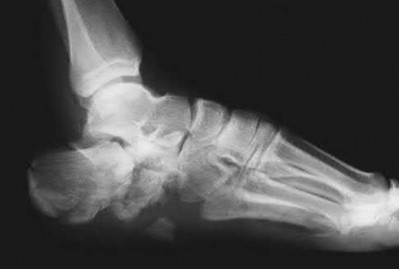

A 25-year-old female is involved in a motor vehicle collision. She presents with the isolated injury seen in Figures A through D. Her leg is swollen but her skin is intact. She has no clinical signs of compartment syndrome. Which of the following treatment options will allow for maintenance of fracture alignment and minimize the risk of soft tissue complications?

The patient presents with a closed distal third metaphyseal-diaphyseal distal tibia fracture with simple intra-articular extension. Immediate intramedullary nailing along with percutaneous fixation of the articular component provides appropriate restoration of length, rotation and alignment and minimizes the risk of wound complication.

Displaced distal third tibia fractures may be associated with simple intraarticular extension. Operative treatment of intra-articular distal tibia fractures has historically been performed with open reduction and internal fixation. Early open reduction and plate fixation of pilon fractures has been associated with high rates of infection and wound complication. In select patterns with simple articular extension, percutaneous screw fixation and medullary nailing may provide appropriate reduction with minimal soft-tissue risk.

Figures A and B demonstrate a distal third tibial shaft fracture with simple intra-articular extension. The axial and coronal CT cuts in Figures C and D further clarify the articular injury. Illustrations A and B demonstrate a comminuted distal third tibial fracture with simple intra-articular extension. Illustrations C and D are fluoroscopic images of the same injury after intramedullary nailing and percutaneous fixation of the articular component.